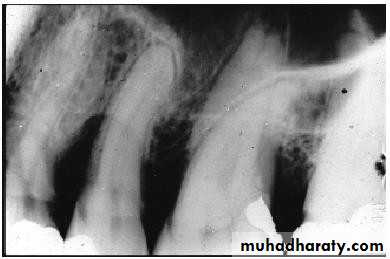

• Periodontal Examination Radiographic Assessment

• Periodontitis

• Healthy Periodontium

• Periodontal Examination• Radiographic Assessment

• Bone Loss• Horizontal Vertical

• Endodontic involvement Root deposits